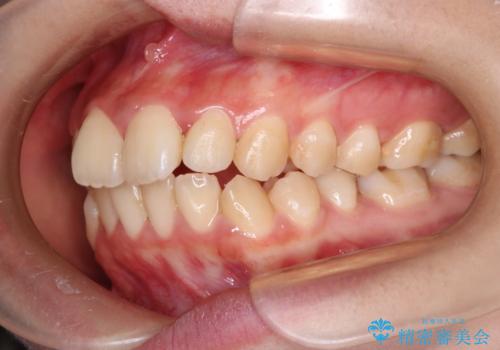

【ハーフリンガル】口元を下げたい!

- ハーフリンガル

- 口元が出ていることを主訴に来院されました。

歯を抜いてスペースを作ることで、前歯を下げることができました。

ハーフリンガルということで治療期間が3年近くかかりましたが、口元もしっかり下がり満足していただきました。